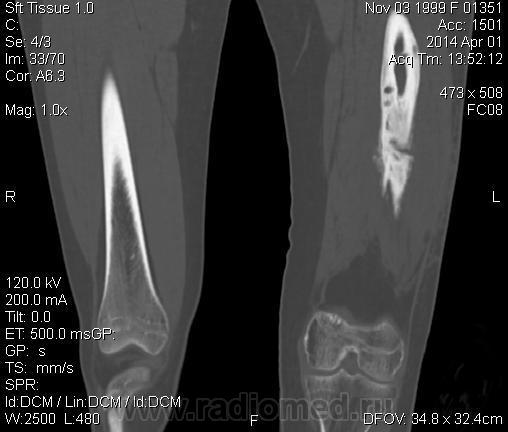

Молодая дама (14 лет) с переломом срдней трети диафиза левого бедра в анамнезе (декабрь 2012 г). Ломала ногу несколько раз в этом месте. Сейчас состояние после МОС. Как следует понимать изменения в кости, формируется ли ложный сустав?

Похоже ложный сустав сформировался. Но при нём обычно большие напластования костной мозоли, здесь их нет. В таких случаях смотрю при скопии подвижность.

Ох, не хочется думать о ложном суставе в 14 лет... По срокам под ложный сустав подходит, он характеризуется замыканием костномозгового канала с формированием подобий суставных поверхностей. У нее же есть хиленькая периостальная костная мозоль по задней поверхности бедра удерживающая отломки в правильном положении. Я склонна думать, что это скорее застарелый перелом (оно же замедленная консолидация). Здесь очень важно посмотреть предыдущие снимки (поиск рефрактуры, либо отсутствия полной консолидации).

Настоящего, родного ложного сустава пока нет, хотя костномозговой канал дистального отломка уже закрыт - образовалась склерозированная замыкательная пластина. Варусная деформация почти в 165 градусов... Я бы заключилась неполной консолидацией и варусной деформацией, прогностически формирование ложного сустава очень вероятно.